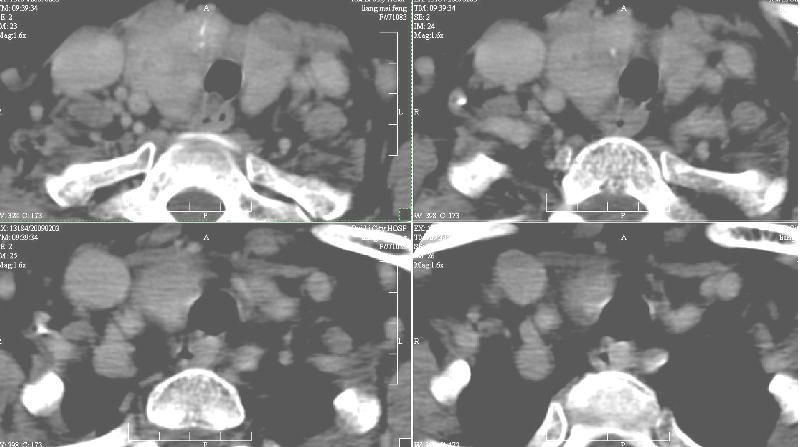

增强:1、双侧甲状腺肿。2、平扫甲状腺内多发占位病变,增强显示不清楚,境界欠清,请结合临床考虑甲状腺瘤。

考虑甲状腺癌!

右侧甲状腺占位及右侧淋巴结肿大,考虑甲状腺癌!期待结果!

强化效果一般,未见明显恶性征象。

1)弥漫性甲状腺肿。2)甲状腺多发性腺瘤?